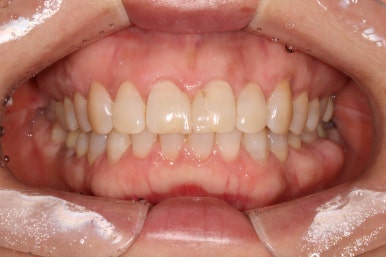

정면에서 본 사진입니다.

잘 모르실 수도 있겠지만, 잇몸이 염증이 생겨 치주염으로 인해 빨갛게 변하신 것을 보실 수 있어요.

즉, 잇몸질환-만성치주염을 갖고 계신 상태였죠.

위 앞니 (중절치)는 치아 사이 틈을 메우기 위해 예전에 레진치료를 받으신 상태였는데, 치료받으신지 오래되어 레진 충전물의 색이 변하고 어색한 모양을 띄고 있습니다.

앞면, 양쪽 옆면 모두 아주 깔끔하게 유지되고 있네요!

기억하고 있으실지 모르겠지만, 전반적으로 나타내고 있던 잇몸의 붉은색도 대부분 사라져 있는 상태입니다.